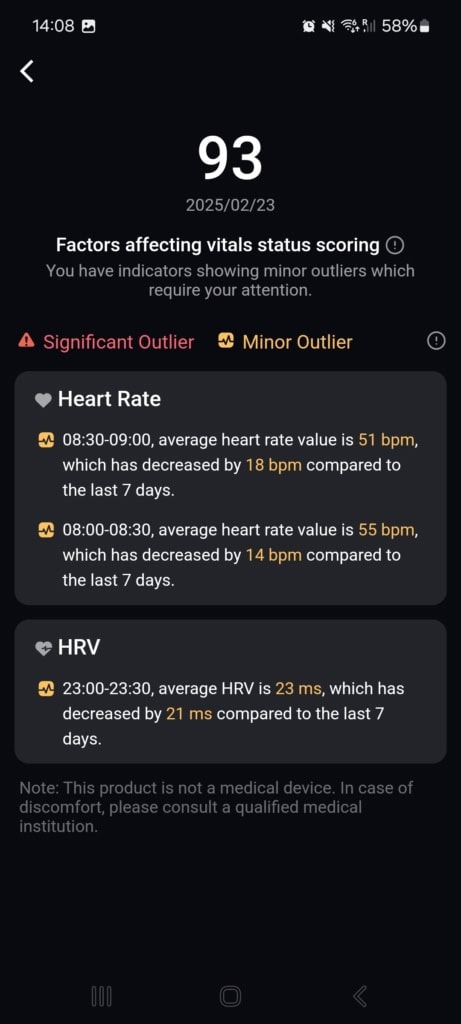

Stan funkcji życiowych (Znaki życia)

W tej części aplikacji dowiesz się o całodziennych wahaniach tętna i jego zmienności, nasyceniu krwi tlenem, częstotliwości oddechów podczas snu i temperaturze snu. Aplikacja porównuje wszystkie te dane z twoją własną referencją z ostatnich 7 do 30 dni oraz z referencyjnymi wartościami medycznymi. Gdy tylko w ciągu dnia lub nocy osiągniesz wartości, które nie mieszczą się w referencyjnych granicach, aplikacja cię o tym poinformuje.

Najczęściej spotykałem się z wyraźnym spadkiem zmienności tętna i wzrostem samego tętna. Te wahania pojawiały się czasem podczas snu, aktywności sportowej lub w przypadkowych sytuacjach, o których nie miałem pojęcia. Mimo że doceniam ten kompleksowy wgląd w moje funkcje życiowe, brakowało mi podczas testowania kontekstu. Funkcja oferuje jedynie wartości i spostrzeżenia, że coś jest nie tak. Nie znalazłem w aplikacji żadnych wskazówek dotyczących możliwych przyczyn ani rekomendacji działań, które mogłyby pomóc przywrócić stan do normy.

Mimo że nietypowe wartości nie mają jasnego kontekstu, aplikacja zwraca na nie uwagę i pyta, co mogło być ich przyczyną (spożycie alkoholu, infekcja, kofeina i inne). W moim przypadku działało to idealnie. Popełniłem błąd dietetyczny, przez który dostałem gorączki i problemów trawiennych. Mój ogólny stan znacznie się pogorszył, co objawiło się wyraźnym spadkiem jakości snu, obniżoną zmiennością tętna i podwyższoną temperaturą ciała. Wszystkie te zmiany zostały przez pierścień i aplikację trafnie rozpoznane i ocenione. Po kilku dniach mój stan się poprawił – również to zostało odnotowane i odpowiednio skomentowane.